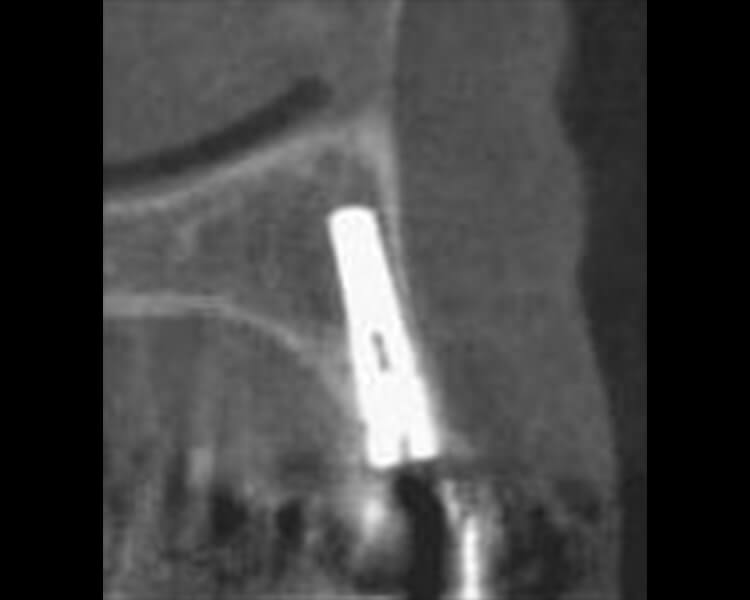

図14‑1 ワルファリン継続したままインプラント埋入手術を行った症例

69歳、女性で、心臓の人工弁置換術後で、ワルファリンを服用していた。

人工弁置換術後でワルファリンを服用している患者は、歯科外科処置時にワルファリンを中断すると、血栓を形成する危険性が高いので、継続下での埋入手術を行った。手術当日に測定したINR値は2.52であった。

図14‑2 切開、粘膜骨膜弁形成。フィクスチャー埋入。

ワルファリン継続したまま1本のインプラント埋入手術(直径3.8、長さ16mm)を行ったが、切開、粘膜骨膜弁の形成、ドリリング、フィクスチャー埋入時いずれも出血で術野が妨げられることはなく、縫合終了時には完全に止血し、後出血もなかった。

図14‑3 術後CT。